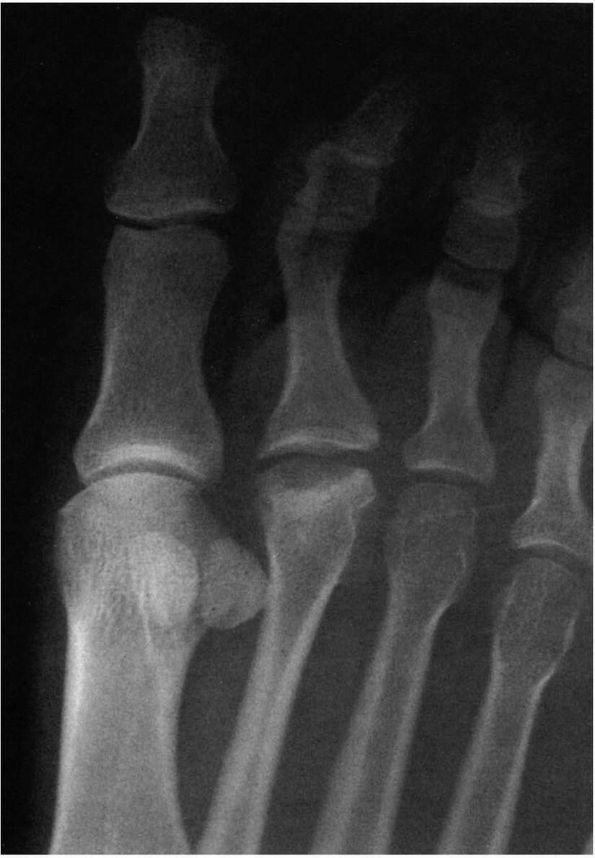

![]() |

FIGURE 21-2.

Radiograph of a hallux valgus deformity. Note the lateral deviation of the proximal phalanx on the metatarsal head, the medial deviation of the metatarsal head, and subluxation of the sesamoids. |